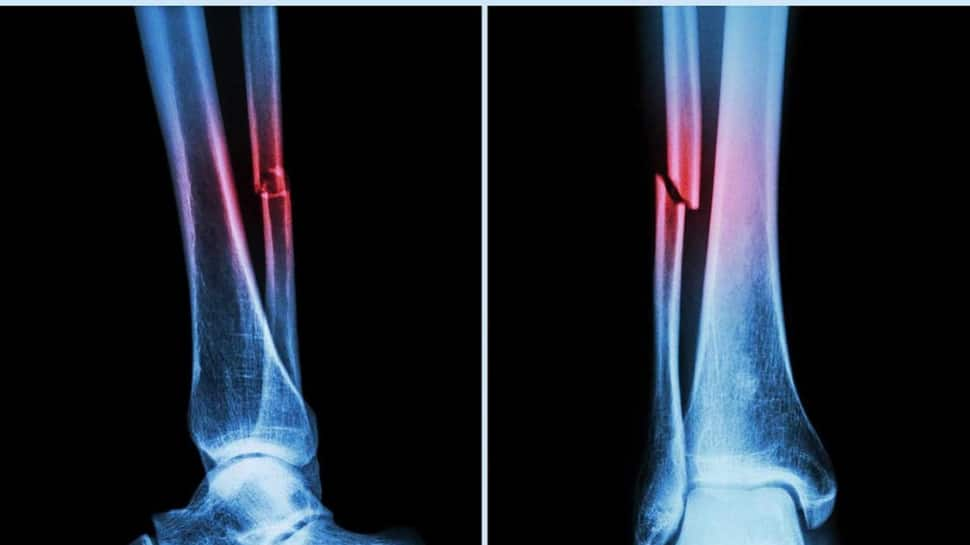

Further research by ECU’s Marc Sim revealed that AAC is not only a cardiovascular risk indicator but also a strong predictor of falls and fractures. In fact, AAC outperformed traditional fall risk factors like bone mineral density and past fall history.

“The higher the calcification in your arteries, the higher the risk of falls and fractures,” Sim said, adding clinicians typically overlook vascular health in fall assessments, and this algorithm changes that.

“Our analysis uncovered that AAC was a very strong contributor to fall risks and was actually more significant than other factors that are clinically identified as fall risk factors.”

Sim said that the new machine algorithm, when applied to bone density scans, could give clinicians more information about the vascular health of patients, which is an under-recognised risk factor for falls and fractures.